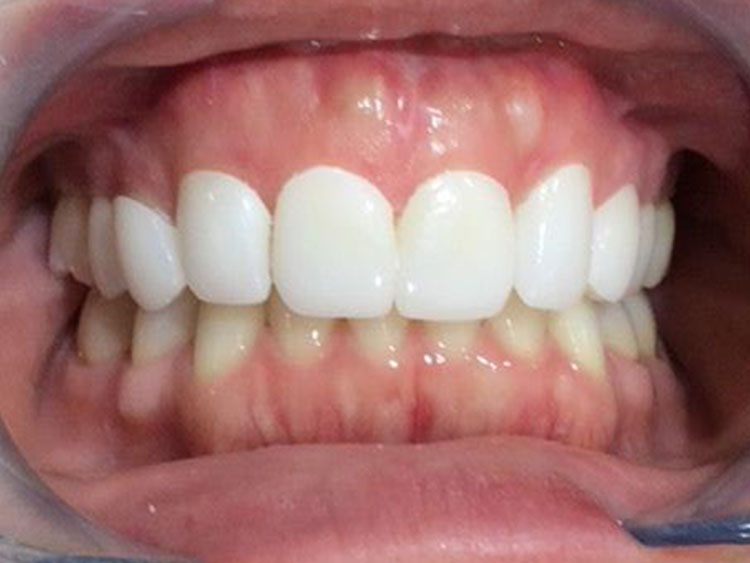

AFTER

20代。 「前歯の傾きが気になる」「下の歯のガタつき」を主訴に来院。 検査の結果、上の前歯が下の前歯を深く覆ってしまう「過蓋咬合(Deep Bite)」の状態であり、見た目だけでなく噛み合わせの機能改善も必要でした。